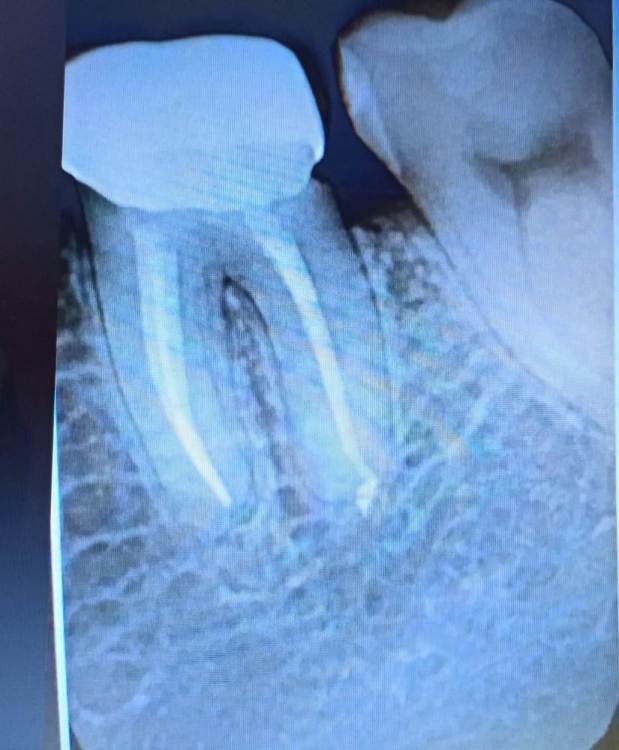

Что видно на снимке? good job? Коронке год, ещё год-два протянет?

Здравствуйте.Уважаемые специалисты,у кого есть опыт лечения, кто с таким сталкивался?  Коронке полтора года,сейчас симптомов по-прежнему никаких нет, только пища застревает, в день по два раза приходится чистить,в принципе как и всем людям. В остальном по зубу и конструкции всё хорошо? Или как возможно видно есть пятна,перфорации или что-то? снимок сделан спустя год.

Может,прогноз какой-то, какие варианты как долго можно протянуть,ухаживая...Удалять очень не хочется, никаких имплантов сейчас не может быть.

если застревает пища, то нужно обратиться к ортопеду, возможно придется переделать коронку для создания хороших контактных пунктов

коронка плохо прилегает и контактный пункт всего скорее или отсутствует или очень слабый если постоянно пища застревает